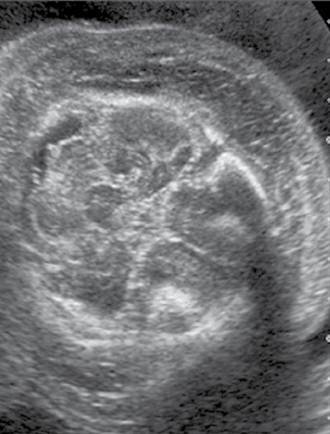

Monochorionic, monoamniotic twin gestation